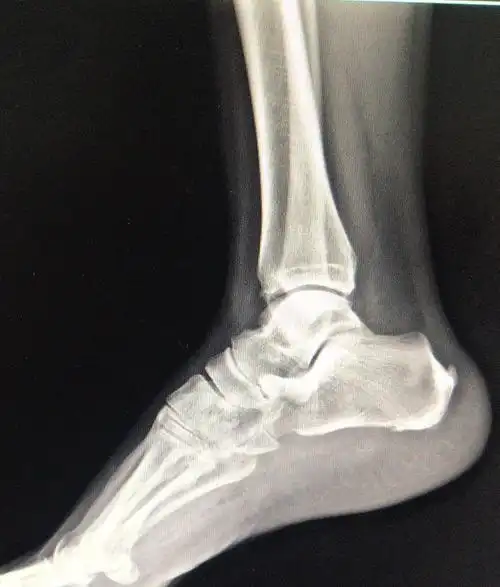

我科开展我院首例关节镜下双侧跟骨骨刺修整术